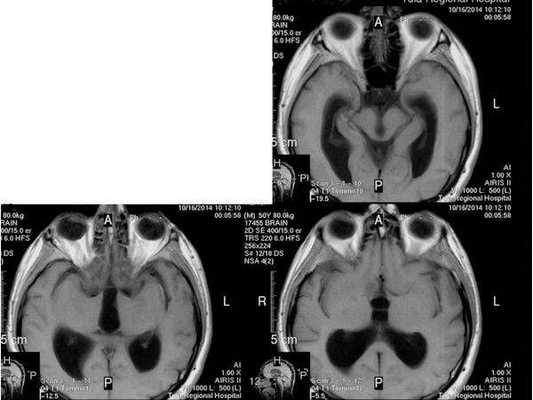

- МРТ в динамике показывает постепенное сужение желудочковой системы на 2 мм. Для сравнения представлены снимки МРТ от 14.05.2013 и от 16.10.2014.

МР-томограмма нормального головного мозга. Серым цветом изображено вещество мозга, белым - ликвор. Нормальная величина жидкостных пространств головного мозга (они щелевидны). Желудочки видны внутри мозга. Субарахноидальные пространства - белая кайма вокруг мозга.

МР-томограммы при внутричерепной гипертензии и гидроцефалии. Результат недостаточного лечения повышенного внутричерепного давления. Видно избыточное скопление ликвора внутри головного мозга (в виде бабочки) и снаружи мозга (широкая белая кайма). Объем мозгового вещества уменьшен - атрофия головного мозга от давления жидкостью.